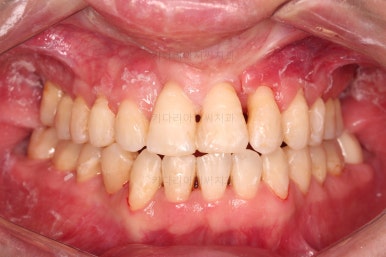

6. 마무리와 치료종료

부산구순구개열교정 종료 시의 입안의 모습입니다.

위아랫니 정렬이 잘 되었고, 치아 갯수가 위아래가 다르지만 교합도 나쁘지 않게 마무리가 되었습니다.

대문니 2개가 예후가 안좋긴 하나 양옆 치아들과 유지철사로 부착해 두어 최대한 오래 조심히 써보기로 했습니다.